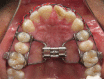

Continuous positive airway pressure (CPAP) is considered first-line treatment in the management of pediatric patients without a surgically correctible cause of obstruction who have confirmed moderate-to-severe obstructive sleep apnea (OSA). The evidence supports its reduction on patient morbidity and positive influence on neurobehavioral outcome. Unfortunately, in clinical practice, many patients either refuse CPAP or cannot tolerate it. An update on alternative approaches to CPAP for the management of OSA is discussed in this review, supported by the findings of systematic reviews and recent clinical studies. Alternative approaches to CPAP and adenotonsillectomy for the management of OSA include weight management, positional therapy, pharmacotherapy, high-flow nasal cannula, and the use of orthodontic procedures, such as rapid maxillary expansion and mandibular advancement devices. Surgical procedures for the management of OSA include tongue-base reduction surgery, uvulopalatopharyngoplasty, lingual tonsillectomy, supraglottoplasty, tracheostomy, and hypoglossal nerve stimulation. It is expected that this review will provide an update on the evidence available regarding alternative treatment approaches to CPAP for clinicians who manage patients with pediatric OSA in daily clinical practice.